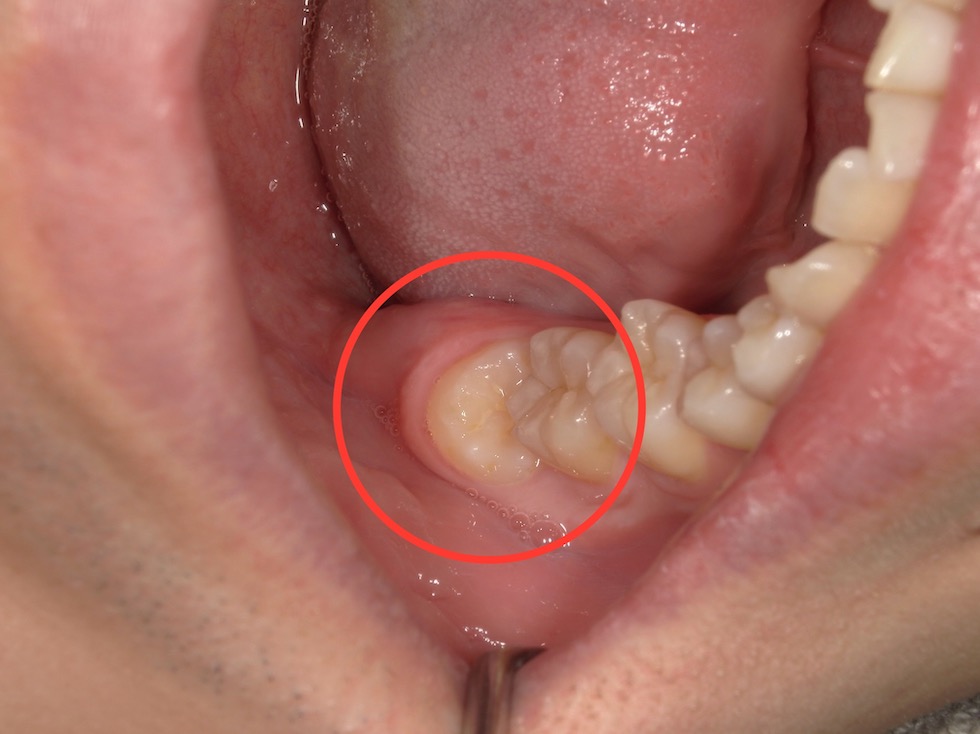

右下の奥歯(親知らず)に食べカスが詰まり歯茎が腫れていました。数年前より繰り返しており、診査の結果、「智歯周囲炎」と診断しました。原因は親知らずであると診断したため抜歯を行うこととなりました。

レントゲンで確認したところ、右下の親知らずは斜めに生えていました。手前には健康な歯があり傷をつけられないため、抜歯する親知らずを分割して抜歯をすることになりました。部分麻酔を行ったのち、初めに歯冠(歯の頭の部分)を2つに割って取り、その後、歯根(歯の根の部分)を引き上げることで抜歯を行いました。傷口がやや広いため、1カ所だけ縫合しました。抜歯後の注意事項をご説明し、抗生物質と鎮痛剤を処方しました。